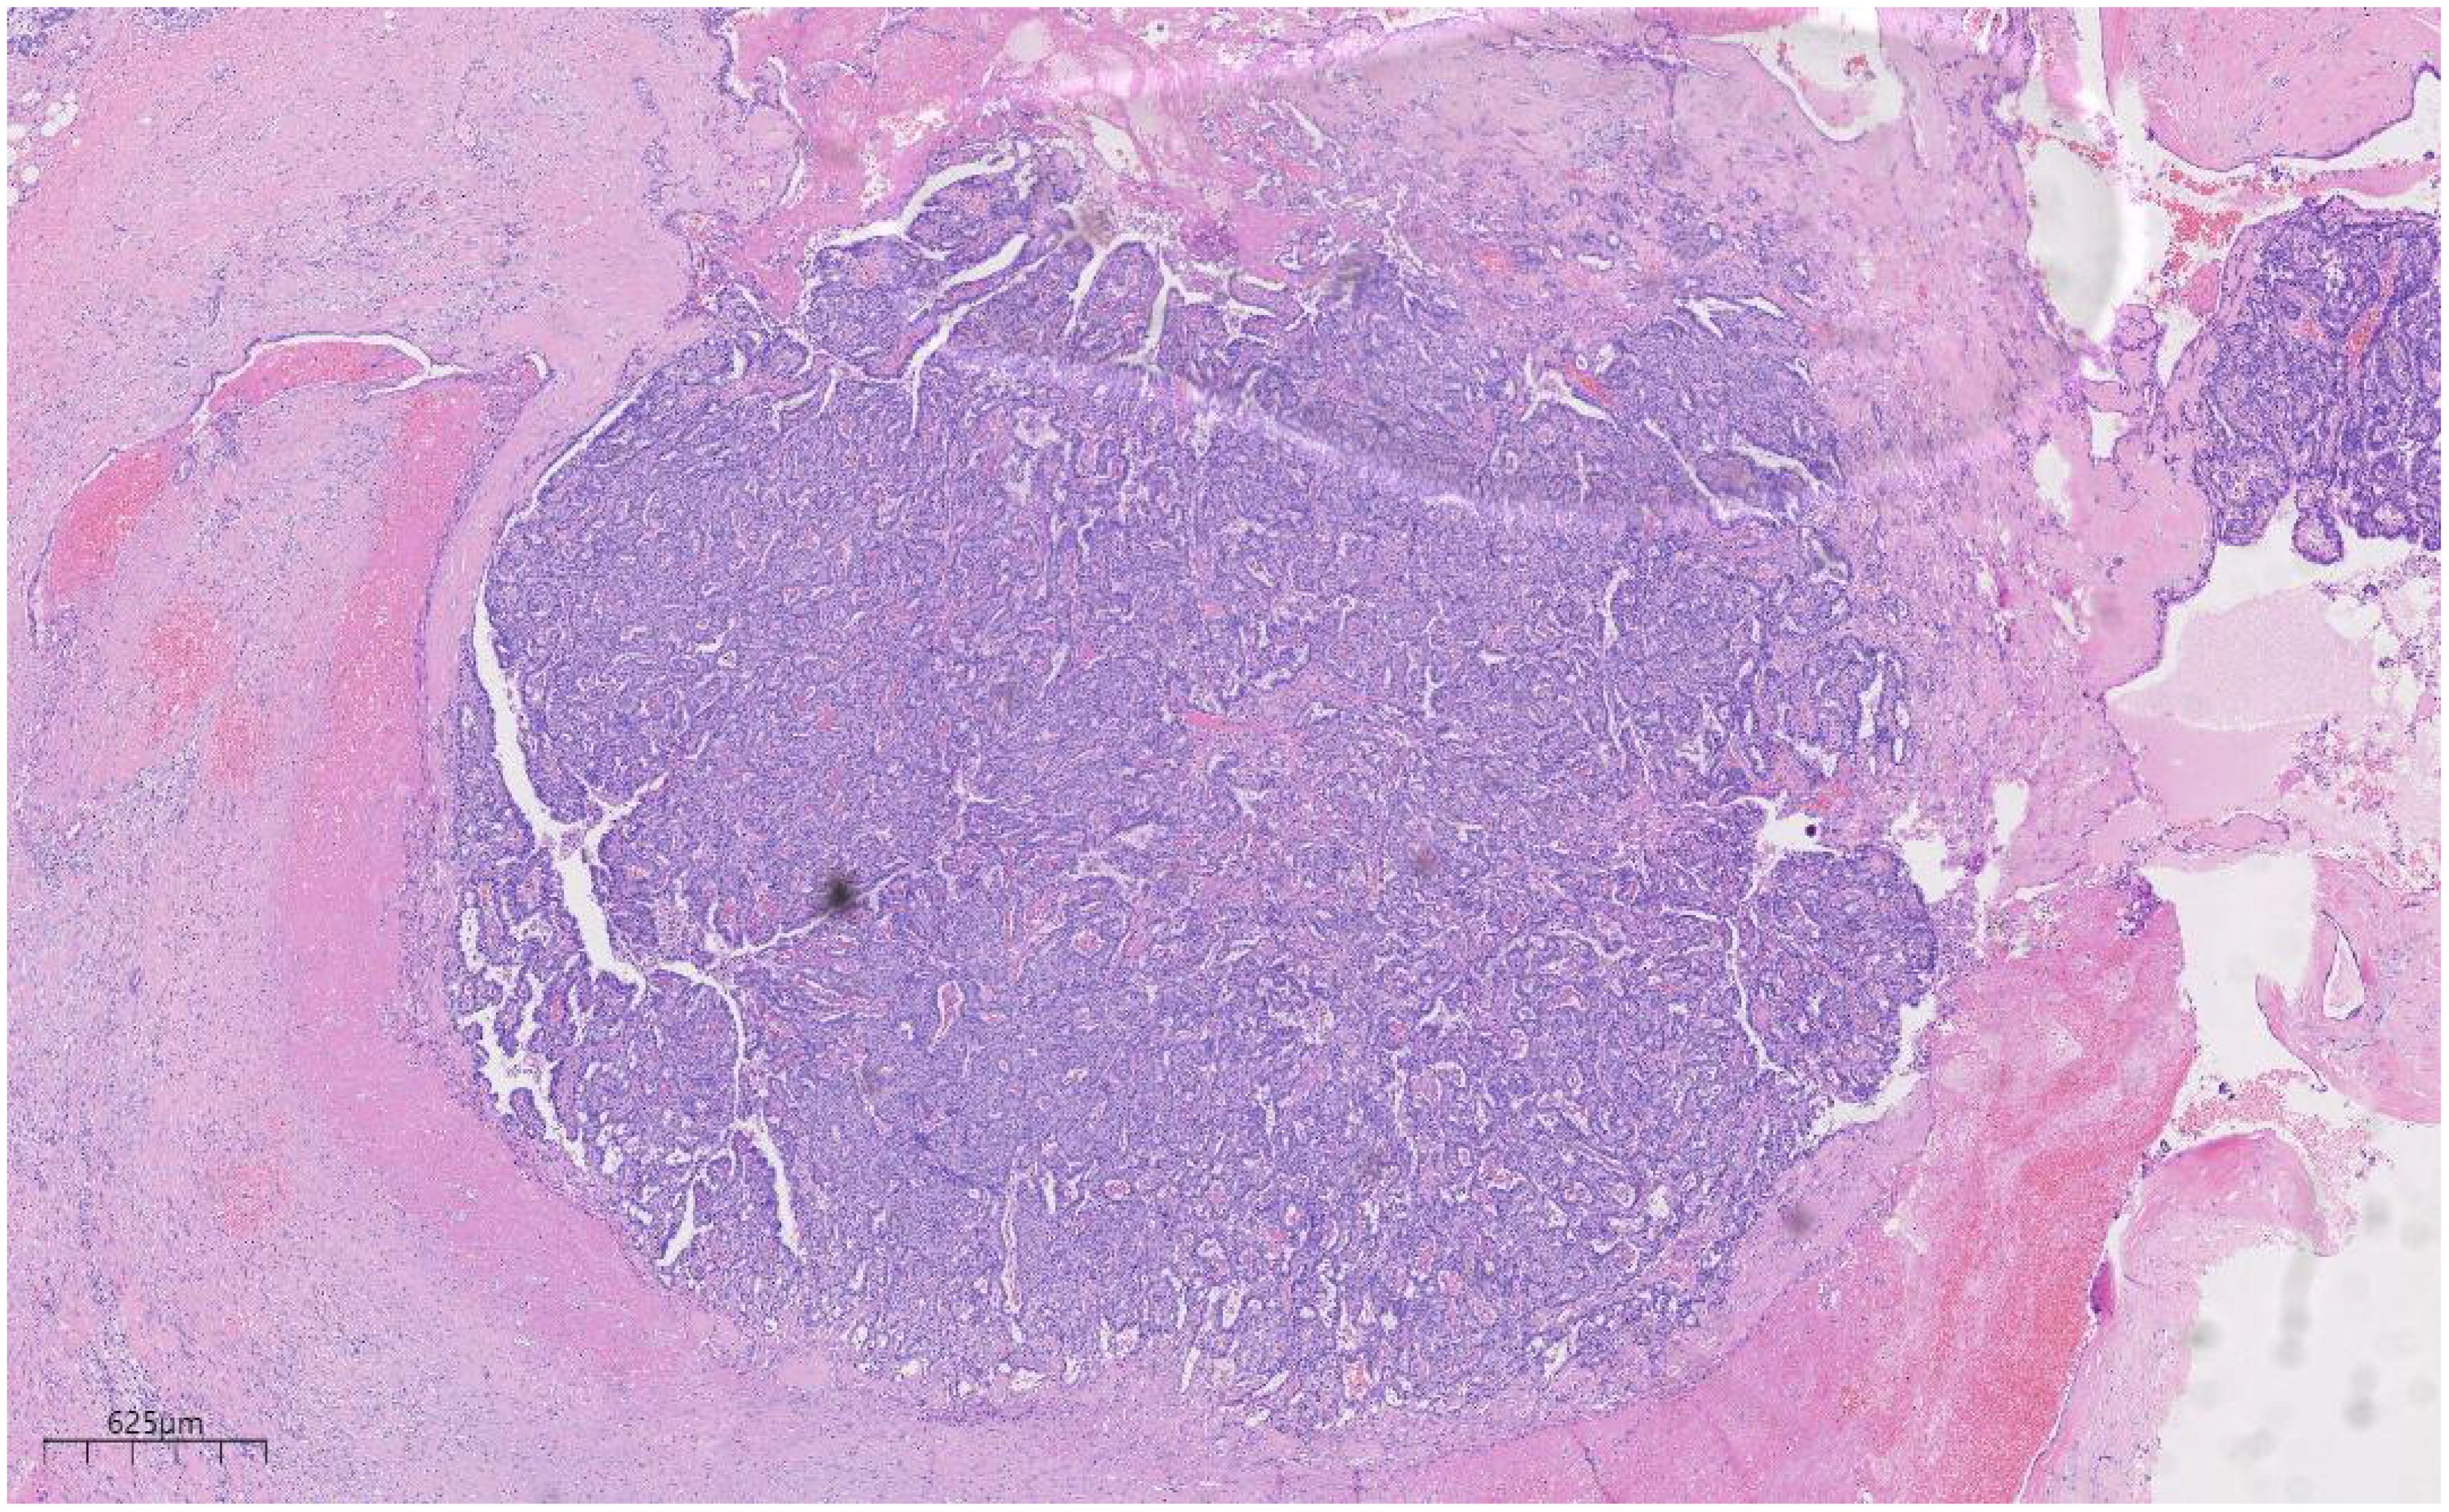

The breast MRI (Figure 1), both with and without contrast administration, identified C-type bilateral breasts with low background enhancement. The outer quadrant of the right breast exhibited multiple areas of abnormal enhancement, nearly including the entire region. Following contrast injection, enhancement appeared markedly irregular, with a significant increase in vascular shadows both within and around the affected areas. The time-signal intensity curve conformed to type II, while diffusion was restricted (1.1). Enlarged lymph nodes in the right axilla, accompanied by surrounding edema and high signal diffusion, indicated multiple regions of abnormal enhancement in the right breast and enlarged axillary lymph nodes.

Figure 1

MRI images of breast tissue. Panel A shows a sagittal view, highlighting internal structures and varying tissue densities. Panel B provides an axial view, displaying the breast and surrounding tissues with distinct areas of brightness and darkness signifying different tissue types.

Figure 1. Bilateral breast c-shaped images with low background enhancement and multiple regional abnormal enhancement areas in the right lateral quadrant of the breast [(A) Sagittal section (B) Transverse section].